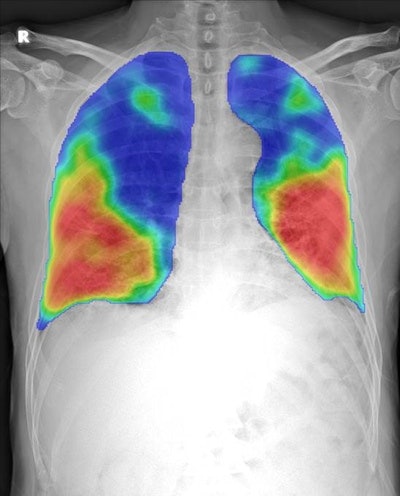

Earlier this month, Thirona and sister company Delft Imaging introduced CAD4COVID-Xray, a software application for helping to triage COVID-19 cases and indicate the affected lung tissue on chest radiographs. CAD4COVID-Xray is built on the technical core of the CAD4TB software, which was developed by Thirona and distributed by Delft for use in tuberculosis screening.

Although the reverse transcription polymerase chain reaction (RT-PCR) test and CT are the preferred options for diagnosing COVID-19, x-ray can be a useful tool in resource-constrained settings. The modality is currently utilized in many countries for front-line triage before any further testing, Delft and Thirona said.